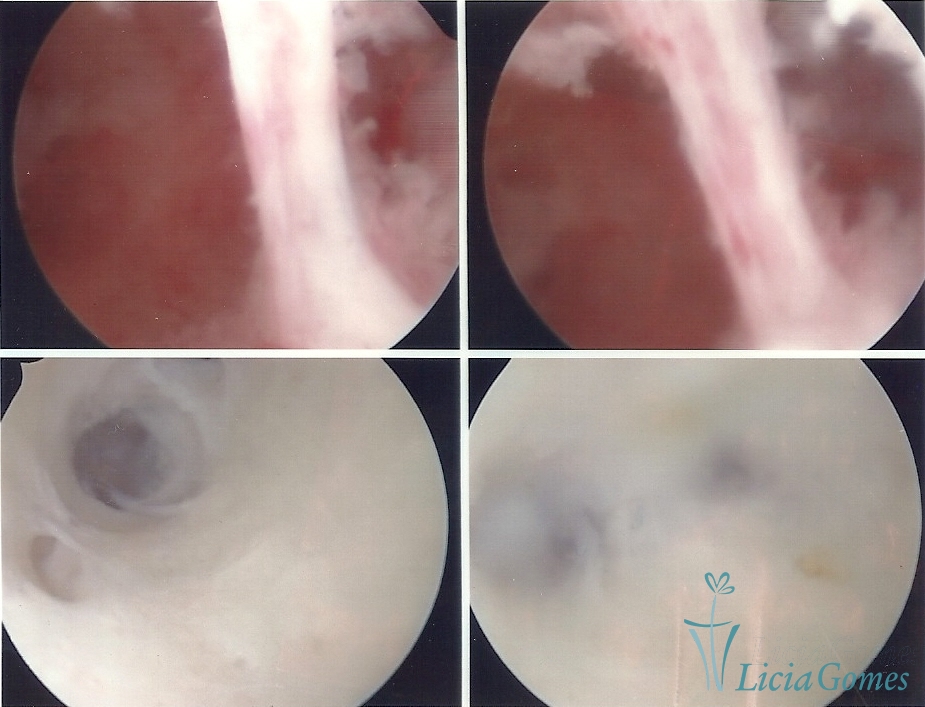

Sinéquia TIPO FIBROSA

• SINÉQUIA TIPO FIBROSA